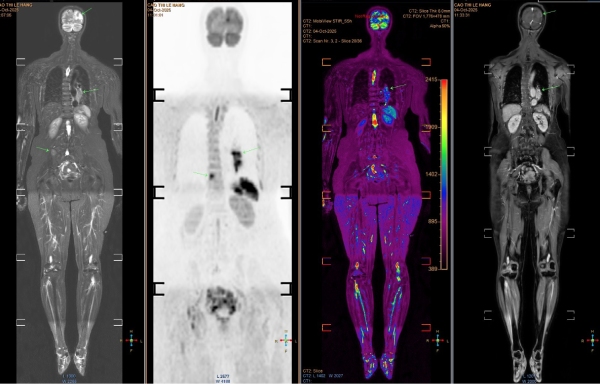

ผลการตรวจ MRI พบรอยโรคแพร่กระจายไปยังสมองหลายจุด และเมื่อถ่ายภาพ CT สแกนทรวงอก ก็พบเนื้องอกขนาดใหญ่ที่ฐานปอดซ้าย ซึ่งยืนยันว่าเป็น มะเร็งปอดระยะลุกลาม ที่ได้แพร่กระจายไปยังอวัยวะต่าง ๆ แล้ว แพทย์ระบุว่าการพยากรณ์โรคค่อนข้างแย่